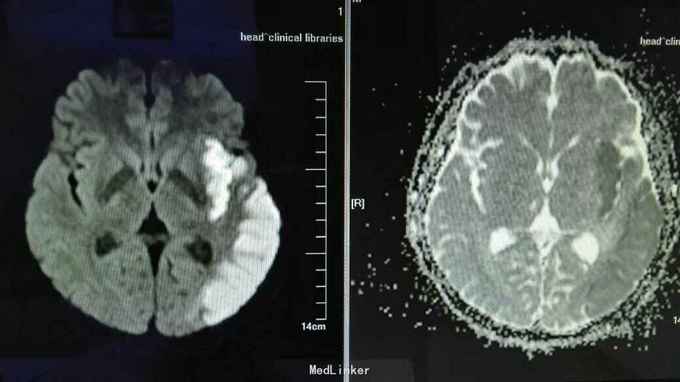

查体:血压190/110mmHg。步入病房,查体合作。心率83次/分,律齐,无病理性杂音,腹部平软,肝脾肋下未触及。神经系统专科查体:神志清楚,混合性失语,双瞳孔同大同圆,直径3.0mm,对光反射灵敏,眼球各方向运动灵活,无眼震及复视,双侧鼻唇沟对称,咽反射(+),伸舌不配合,右侧肢体肌力4+级,左侧肢体肌力5级,肌张力正常,肱二头肌、肱三头肌肌腱及膝反射、跟腱反射均对称,感觉和共济运动检查未见异常不配合,Hoffmann征L(-),R(-),病理征:Babinski征L(-),R(-),颈无抵抗,Kernig征(-)。 辅助检查:头颅MRI扫描示:左侧大面积脑梗塞,右侧腔隙性脑梗塞,左侧蝶窦内长T1长T2信号,囊肿?。心电图提示:窦性心律,T波低平。

诊断:1.脑血栓形成 2.高血压病3级 极高危 治疗:给予抗血小板、改善循环、营养神经、稳定斑块、降压治疗。